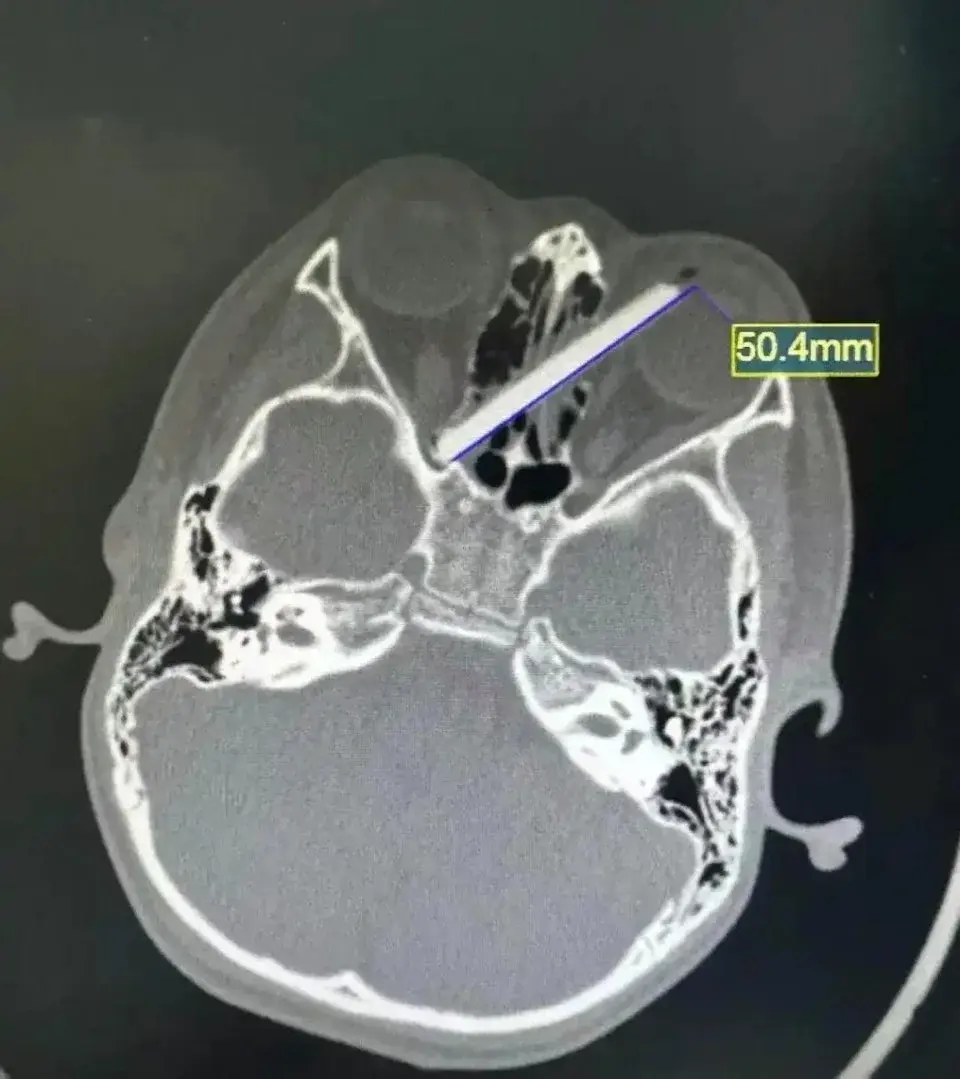

เหตุการณ์เริ่มต้นจากการที่เด็กชายถือตะเกียบไม้ขณะวิ่งเล่นและเกิดเสียหลักล้มคว่ำหน้า แรงกระแทกทำให้ตะเกียบหักและส่วนปลายแหลมทิ่มทะลุเข้าไปในเบ้าตาซ้ายอย่างรุนแรง ผลการเอ็กซเรย์ (X-ray) เผยให้เห็นภาพที่น่าตกใจ เนื่องจากปลายตะเกียบฝังลึกเข้าไปในกะโหลกศีรษะ เฉียดเส้นประสาทตาและหลอดเลือดสำคัญไปเพียงนิดเดียว ซึ่งหากมีการขยับเขยื้อนผิดพลาดอาจทำให้เด็กพิการทางสายตาถาวรหรือเป็นอันตรายถึงชีวิต